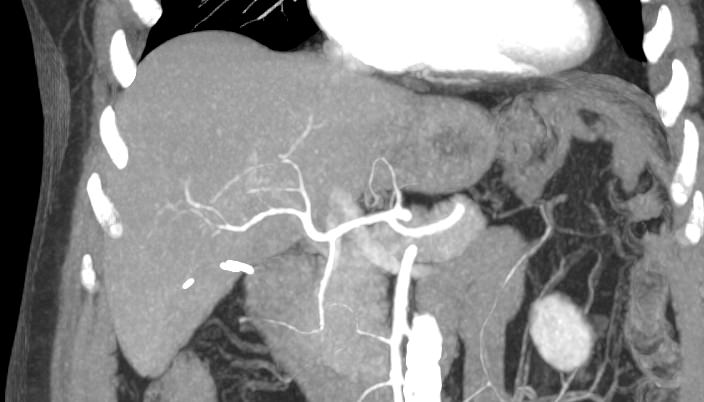

Печеночная ткань имеет обильное кровоснабжение, поэтому часто ультразвуковая диагностика заболеваний печени затруднена. Одним из наиболее информативных методов диагностики является мультиспиральная КТ печени, которая может проводиться в стандартном режиме и с внутривенным болюсным контрастированием. Введение йодсодержащего контрастного вещества значительно повышает диагностическую ценность компьютерной томографии и позволяет, в частности, выявить злокачественное образование на ранней стадии, отличить доброкачественный процесс от злокачественного, визуализировать изменения внутрипеченочных желчных протоков и многие другие патологические процессы.

В нашей клинике сканирование печени выполняется на современных компьютерных томографах экспертного класса TOSHIBA AQUILION, которые производят послойное сканирование исследуемого органа с последующей цифровой обработкой полученных данных для создания трехмерных изображений печени высокого качества и контрастности. Увеличенное количество детекторов, вмонтированных в аппараты, обеспечивает быстрое время исследования и пониженные дозы рентгеновского излучения, получаемого пациентом.